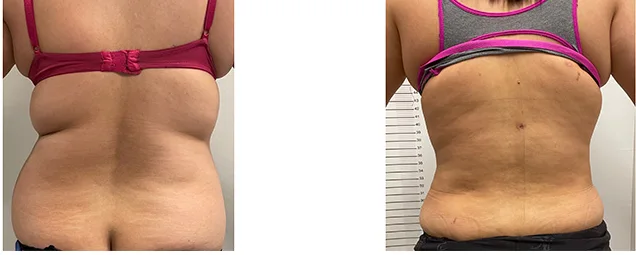

Vaser Liposuction & J-Plasma in Jordan | Cost & Results | Naim Yassin

Vaser Liposuction in Jordan | Naim Yassin Home > Liposuction Vaser Liposuction & J-Plasma High Definition Sculpting with Skin Tightening Technology. Free Body Assessment Advanced 360° Sculpting We combine Vaser technology to melt fat gently with J-Plasma (Renuvion) to tighten the skin immediately. This is ideal for sculpting the abdomen, flanks (love handles), and back […]